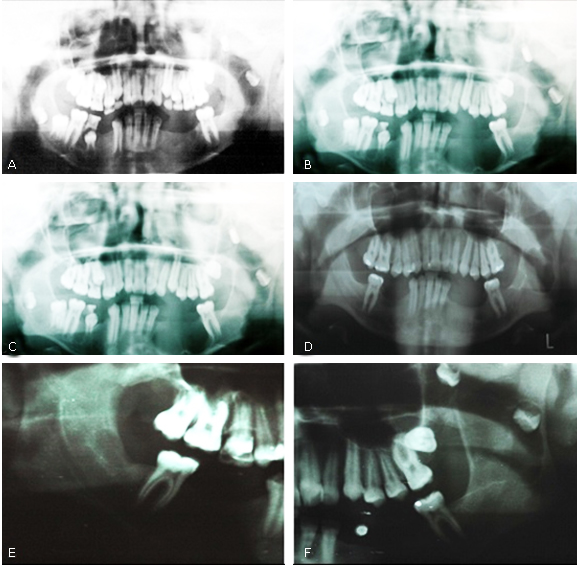

No controle periódico de outubro de 2005 (Fig. 3, A), março de 2006 (Fig. 3, B) e abril de 2007 (Fig. 3, C) foi realizado radiografia panorâmica de rotina e identificado recidivas de lesões em mandíbula. O paciente foi submetido a intervenção cirúrgica em abril de 2007 para remoção das lesões. Em setembro de 2008 através da radiografia panorâmica de rotina (Fig. 3, E e F) foi observado que as lesões associadas as unidades 28 e 38, ambas se encontravam em uma posição favorável para remoção. Foi realizado intervenção cirúrgica e encaminhado para o histopatológico, confirmando novamente o diagnóstico de queratocisto odontogênico.

Fig. 3 - A: Radiografia panorâmica mostrando a recidiva das lesões, em outubro de 2005; B: Radiografia panorâmica mostrando a recidiva das lesões em março/2006; C: Radiografia Panorâmica evidenciando o aumento considerável das lesões em abril de 2007; D: Radiografia panorâmica mostrando a recidiva das lesões- dezembro 2011; (E e F): Radiografia Panorâmica, mostrando recidiva das lesões, e localização favorável das unidades 28 e 38 em setembro/2008.

O paciente foi avaliado em agosto de 2010 e demonstrou um desenvolvimento músculo esquelético compatível com a idade. Durante acompanhamento em dezembro de 2011, ao realizar exame físico, foi possível observar o surgimento de depressões palmares e, durante a análise radiográfica (Fig. 3, D) verificou-se presença de duas lesões recidivantes localizadas no lado esquerdo de mandíbula.

Em janeiro de 2012 o paciente foi submetido a uma nova intervenção cirúrgica para remoção dessas lesões e encaminhadas para o histopatológico, que novamente evidenciou queratocisto odontogênico. Atualmente o paciente encontra-se em proservação na Universidade Estadual de Feira de Santana na Bahia.